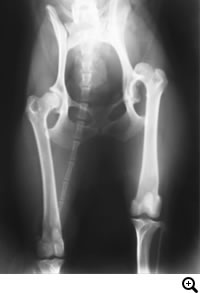

THR(Total Hip Replacement)/ 股関節全置換術

Micro THR(Micro Total Hip Replacement)/ 小型犬・猫用股関節全置換術

全股関節置換術は股関節形成不全やその他の股関節の異常(レッグペルテス、骨頭骨折等)に対して行われる根治的治療法で、機能の回復に関しては現在のところ最もすぐれた治療法です。機能しない、あるいは痛みを持つ股関節をチタンの人工関節に取り替える方法です。6カ月齢からあらゆる年齢で可能な手術です。